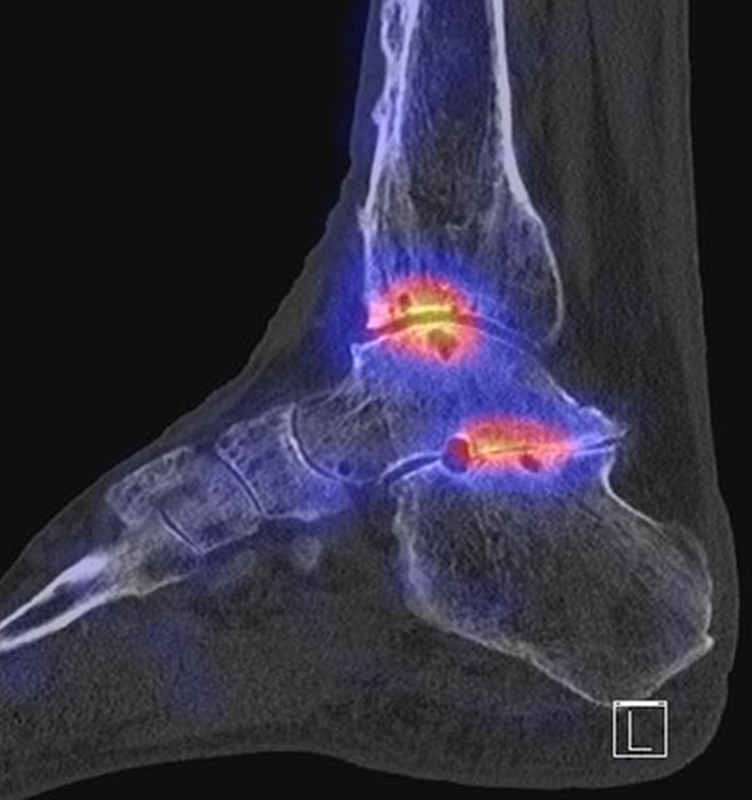

Beispiele für SPECT/CT-Untersuchungen nach OSG-TEP sind in den Abbildungen 6.1. bis 6.3. abgebildet.

Gurbani et al. evaluierten 37 Patienten mit schmerzhaften Sprunggelenkprothesen mit SPECT/CT und korrelierten die Ergebnisse mit klinischen und intraoperativen Befunden. Die SPECT/CT-Ergebnisse korrelierten zu 89,2 % (33/37 Pat.) mit der definitiven Diagnose. 28 Patienten wurden operativ revidiert und der Vergleich der SPECT/CT-Befunde mit den intraoperativen ergab eine Übereinstimmung von 92,9 % (26/28 Pat.). Die SPECT/CT identifizierte in den meisten Fällen aseptische Lockerungen (12/33 Pat.) und Impingement (11/33 Pat.). Seltenere Diagnosen waren Fehlstellungen (4/33 Pat.), Zystenbildungen (2/33 Pat.), subtalare Arthrosen (2/33 Pat.) und Infektionen (2/33 Pat.) 51.

Die Autoren beschreiben einen Fall, der neben einem Fokus am lateralen Malleolus auch eine starke flächige Anreicherung am talaren Prothesen-Knochen-Interface 17 Monate nach TEP-Implantation aufwies, so dass neben dem Verdacht auf ein laterales Impingement auch der Verdacht auf eine Lockerung der talaren Prothesenkomponente geäußert wurde. Intraoperativ bestätigte sich die Lockerung der talaren Prothesenkomponente nicht, sondern nur das laterale Impingement, welches mittels Debridement erfolgreich therapiert wurde 51. Da der Pat. bereits vor der TEP-Implantation eine Triple-Arthrodese erhalten hatte (welche im SPECT/CT unauffällig war), kann eine solche flächige Mehrspeicherung auch als weitgehend asymptomatische Stressreaktion gewertet werden.

Mertens et al. 52 berichten unter Anwendung eines standardisierten Auswerte-Schemas über eine Treffsicherheit von 96 % (Sensitivität 100 %, Spezifität 80 %) des SPECT/CT zur Diagnose der Ursachen für eine schmerzhafte Sprunggelenkprothese (n=24). Der SPECT/CT-Befund führte in 86 % zu einer spezifischen Therapie, welche in 83 % der Fälle zum Therapieerfolg führte.

Eine Analyse von Mason et al. 53 von 14 Patienten mit schmerzhaften Sprunggelenksprothesen, welche mittels SPECT/CT untersucht wurden, fanden in 13/14 Patienten ein SPECT/CT-Korrelat für die Beschwerden, wobei bei 12 Patienten der Fokus talar medial lokalisiert war. 8 Patienten wurden operativ revidiert und der Fokus entsprach einer verminderten bzw. fehlenden ossären Integration der talaren Prothesen-Komponente.